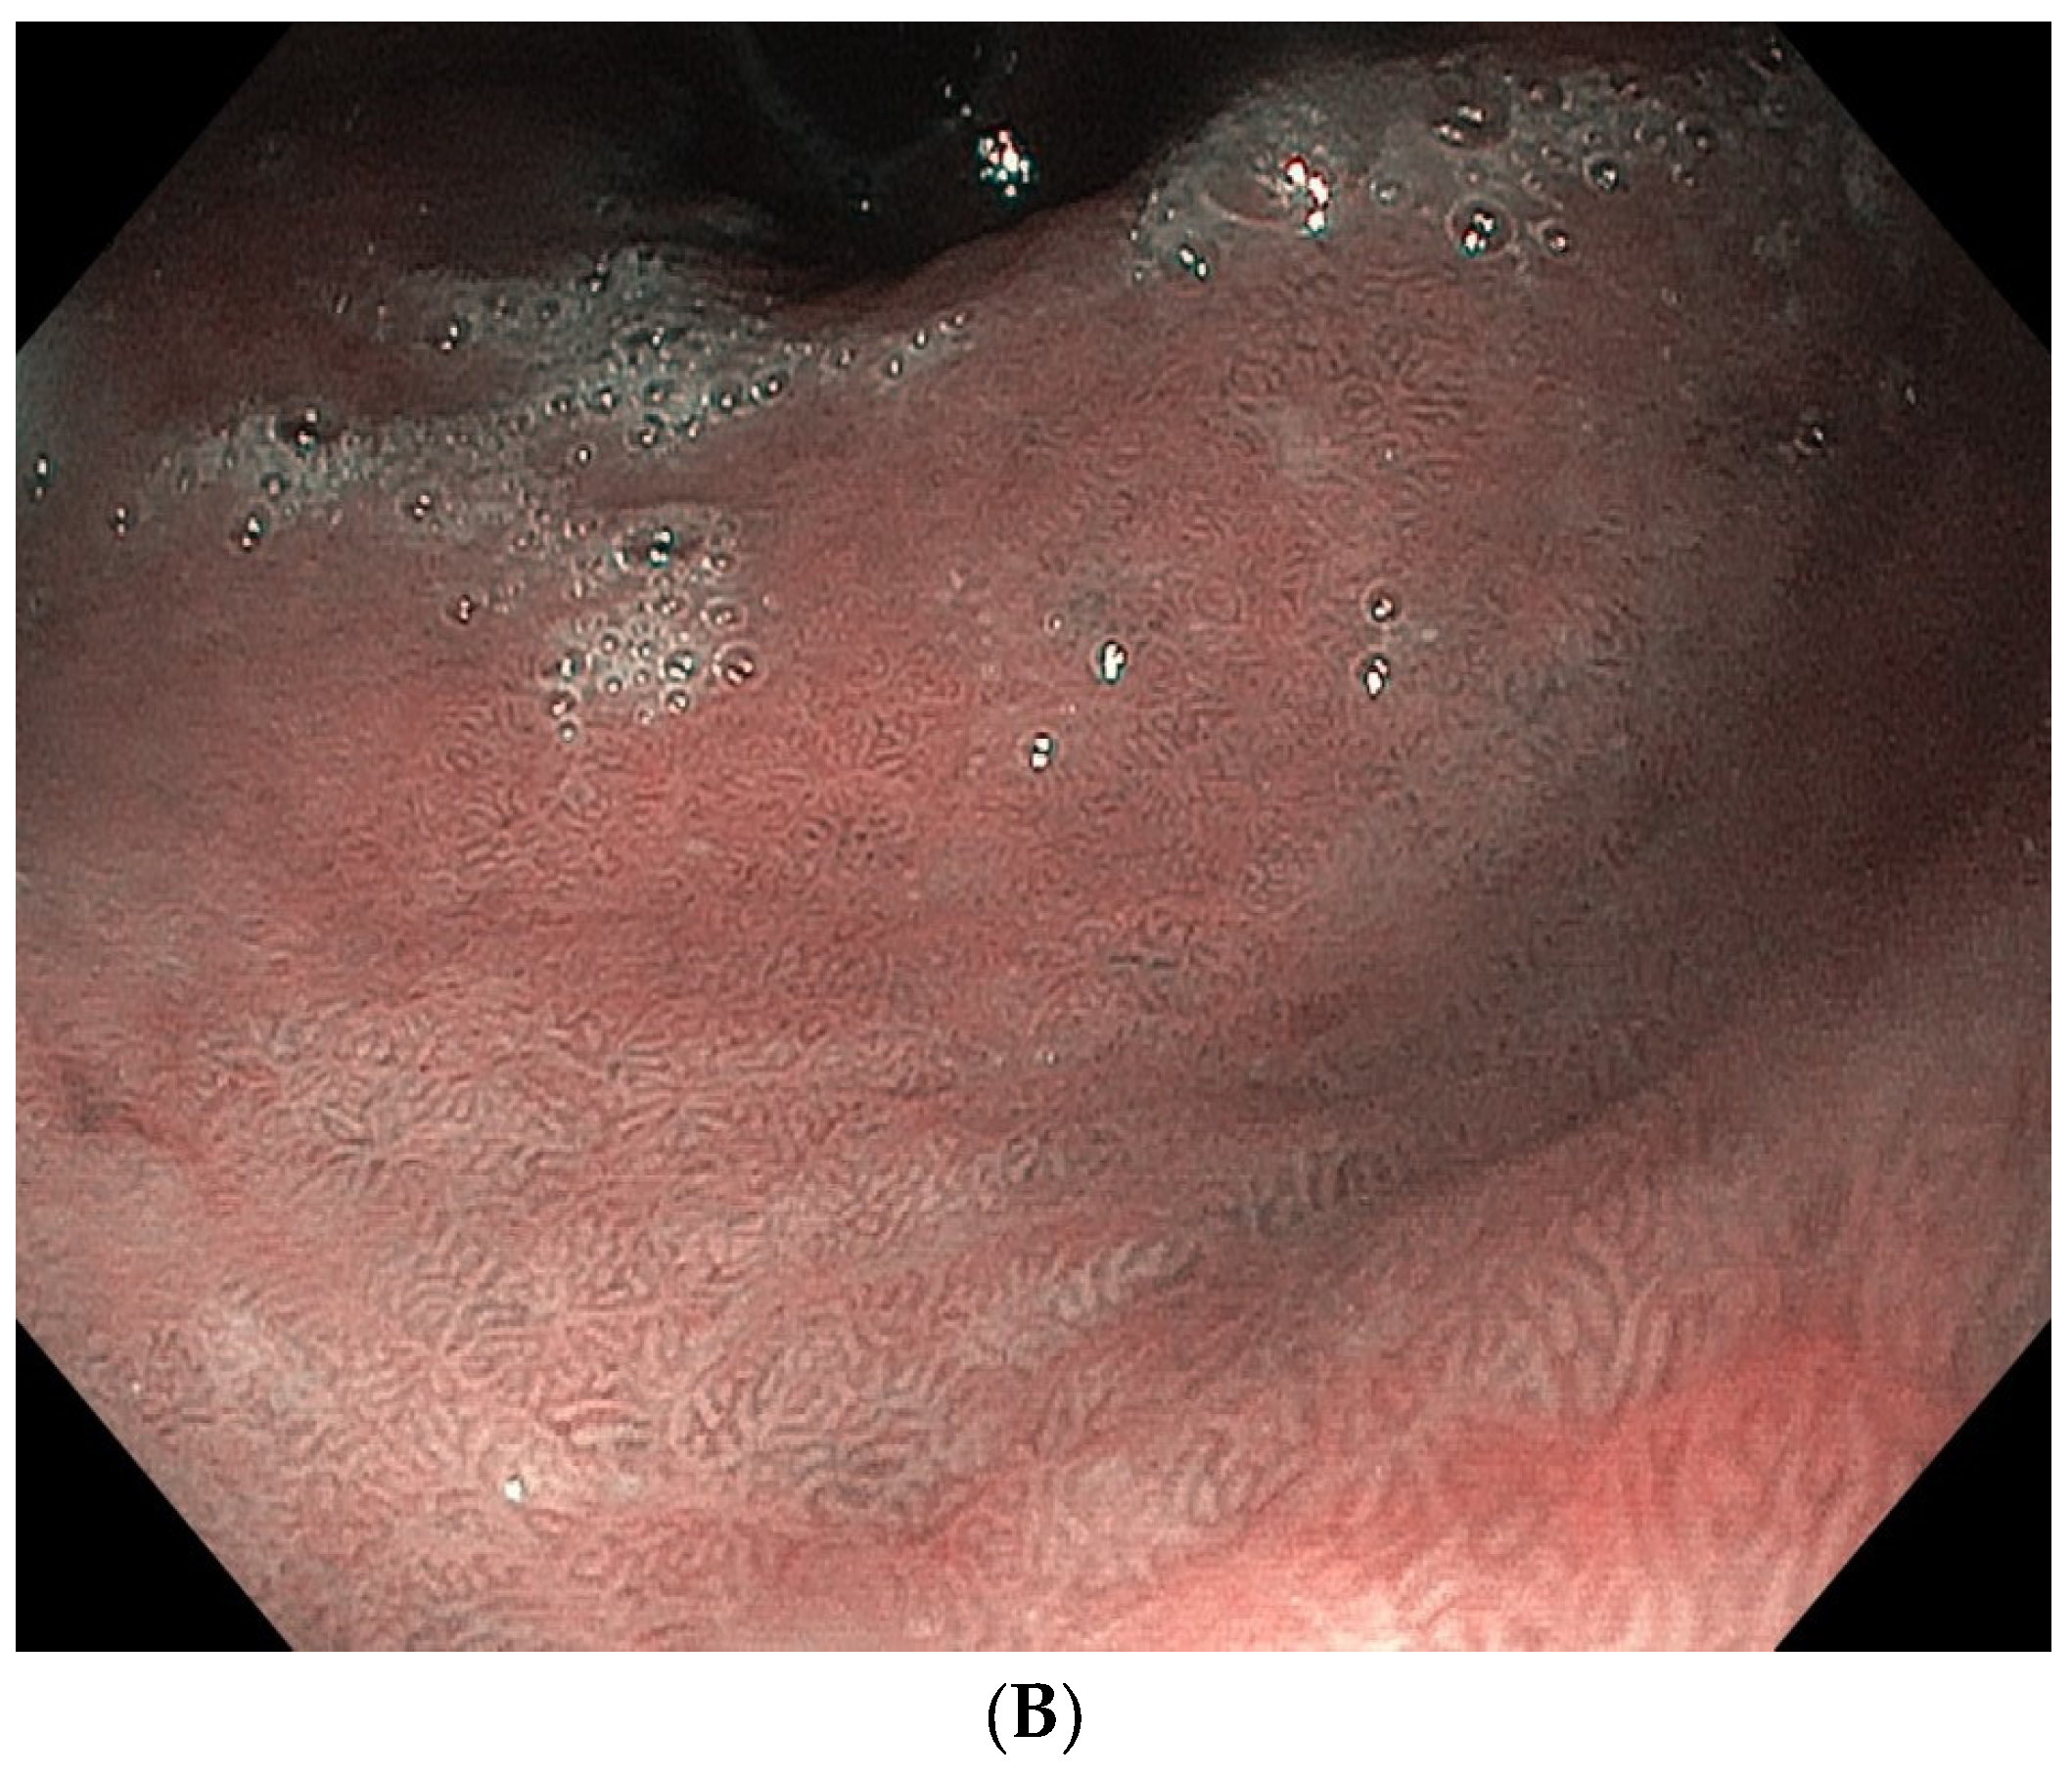

- Esposito, G.; Pimentel-Nunes, P.; Angeletti, S.; Castro, R.; Libânio, D.; Galli, G.; Lahner, E.; Di Giulio, E.; Annibale, B.; Dinis-Ribeiro, M. Endoscopic grading of gastric intestinal metaplasia (EGGIM): A multicenter validation study. Endoscopy 2019, 51, 515–521. [Google Scholar] [CrossRef] [PubMed]